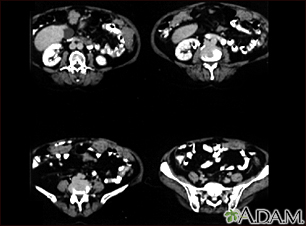

Peritoneal and ovarian cancer, CT scan